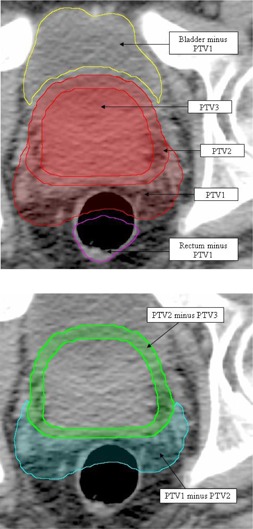

The first step of the planning process is contouring. In addition to standard contours, such as the body, planning target volumes (PTV) and organs at risk (OAR), additional structures are created to aid in the optimization process. This approach is similar to the use of complementary contours used for IMRT planning to improve spatial targeting of dose, henceforth referred to as virtual contours. Examples are shown in Fig. 2. In general, a virtual contour is created for any overlap between PTV and OAR (Fig. 2(a) and, if multiple dose levels exist in the target (e.g., ), any overlap between the PTVs (Fig. 2(b). These virtual contours are essential for the planning strategy. The virtual OAR structures allow for improved sparing of the associated OAR while not giving conflicting optimization inputs. The PTV rings are necessary due to the fact that all PTVs occupy the same physical space and therefore nonconflicting objectives can be applied to each individually to reduce hot areas and improve homogeneity in the more superficial PTV areas.

Figure 2.

Virtual contours, as indicated by arrows: (a) showing all three PTVs and two virtual structures representing the OAR (bladder and rectum) minus the largest volume PTV, plus an extra margin of 3 mm; (b) two virtual PTV structures (PTV1 minus PTV2 (cyan) and PTV2 minus PTV3 (green)).